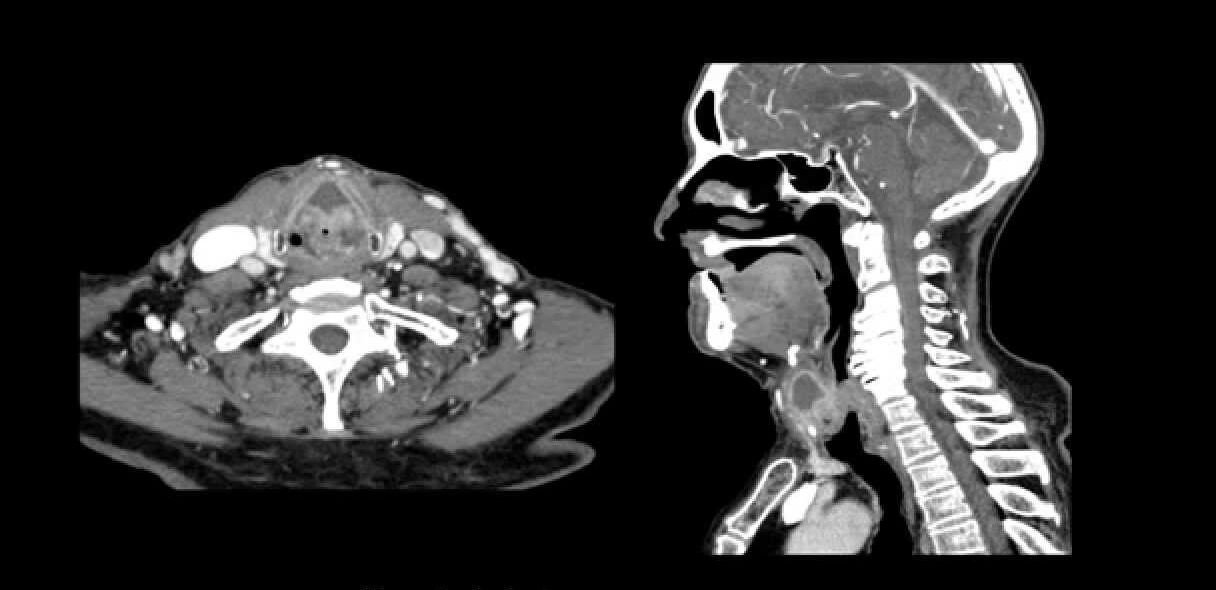

Un examen de tomografía axial computarizada (TAC) cervical es una herramienta de diagnóstico por imagen que permite a los médicos visualizar las estructuras óseas y los tejidos blandos del cuello. Este procedimiento utiliza una serie de rayos X tomados desde diferentes ángulos y los combina con tecnología informática para crear imágenes transversales detalladas.

Un TAC cervical, también conocido como tomografía computarizada de cuello, produce imágenes detalladas de la médula espinal, las vértebras cervicales (los huesos del cuello), los nervios, los vasos sanguíneos y otros tejidos blandos de la zona. Se diferencia de una radiografía tradicional en su capacidad para mostrar secciones transversales, lo que ofrece una perspectiva tridimensional del interior del cuerpo. Piense en ello como cortar un pan por la mitad para ver su interior, en lugar de solo verlo desde fuera.

La mesa se moverá a través del escáner mientras el tubo de rayos X gira a su alrededor. Escuchará ruidos de zumbido y clic mientras se toman las imágenes. Es fundamental permanecer completamente quieto durante el escaneo para evitar imágenes borrosas. El tecnólogo lo supervisará desde una sala contigua y se comunicará con usted a través de un intercomunicador. Es posible que le pidan que contenga la respiración por periodos breves.